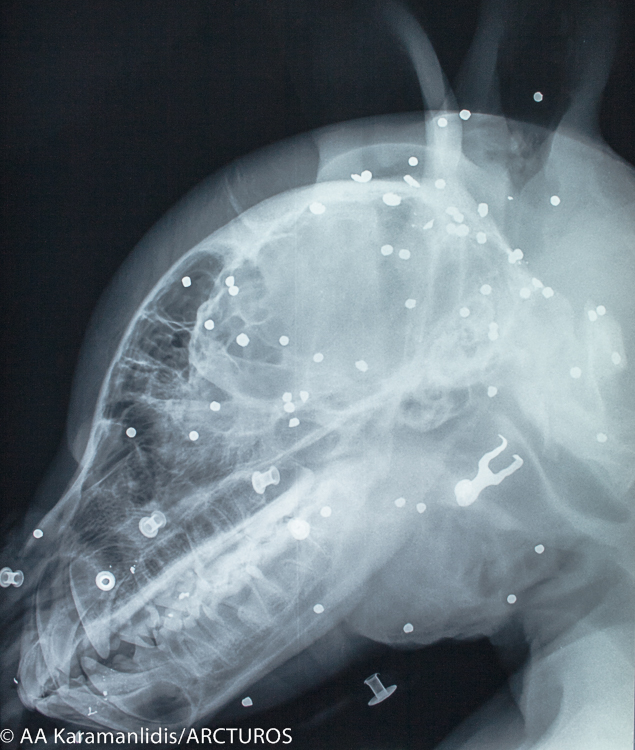

Ο “Γιώργος” μεταφέρθηκε, προχθές, από την Ομάδα Άμεσης Επέμβασης του Αρκτούρου στη Μονάδα Εξωτικών και Άγριων Ζώων και στη Μονάδα Αναισθησιολογίας και Εντατικής Θεραπείας της Κτηνιατρική Σχολής του ΑΠΘ για τις απαραίτητες εξετάσεις. Έπειτα από κλινική εξέταση και τη λήψη ακτινογραφιών διαπιστώθηκε κρανιοεγκεφαλική κάκωση, ενώ παράλληλα βρέθηκαν και άφθονα βλήματα πυροβόλου όπλου στην περιοχή της κεφαλής και του θώρακα.